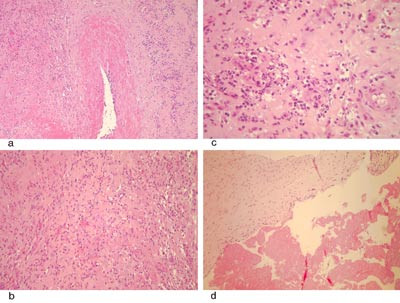

Histologisk undersøkelse av det eksiderte vevet viste betennelsesforandringer som ved infeksiøs endokarditt (fig 4), men det var ikke tegn til bakterier, verken ved dyrking eller mikroskopi. Polymerasekjedereaksjon av det eksiderte vevet var negativ med henblikk på Mycoplasma og Chlamydia. Myksom og andre tumorer kunne utelukkes.

Selv om man kan stille diagnosen endokarditt med kliniske kriterier, er det klargjørende å få den bekreftet ved et eventuelt kirurgisk inngrep. Den makroskopiske vurderingen i forbindelse med operasjonen, samt de mikrobiologiske analysene og de histologiske undersøkelsene av det eksiderte vevet, skal bekrefte diagnosen.

Histologi

Den histologiske undersøkelsen av det eksiderte vevet hos vår pasient viste en betennelsesprosess som kunne passe med infeksiøs endokarditt (fig 4), men uten at det ble påvist bakterier ved dyrking eller mikroskopi. Det var en viss mulighet for vaskulitt, men denne hypotesen lot seg ikke bekrefte med tilleggsundersøkelser. Resultatet av de makroskopiske og mikroskopiske undersøkelsene av det eksiderte vevet gir derfor grunnlag for å tolke tilstanden som infeksiøs endokarditt.